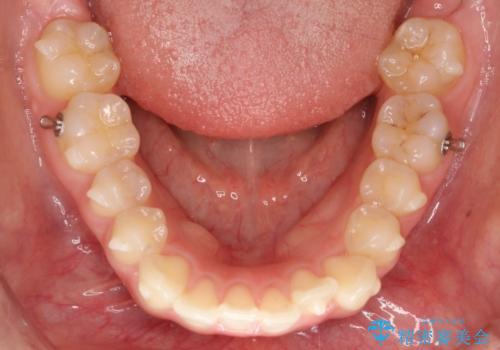

- 前歯が出ていることを主訴に来院されました。

奥歯を後ろに動かしながらスペースを作ることで、前歯を下げることができ患者さんにも満足していただきました。

治療中に顎間ゴムを使用していただいたおかげで、スムーズに治療を行うことができました。